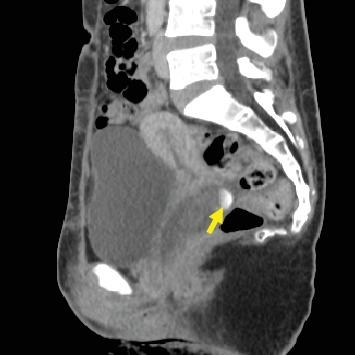

Pseudoaneurysms generally develop when an arterial puncture site is inadequately sealed. We encountered a case of vaginal pseudoaneurysm that developed 3 years after cesarean section in a 35-year-old gravida 7 para 4 woman who was prescribed with anticoagulant and antiplatelet drugs after surgeries for ventricular septal defect and aortic valve replacement. Pelvic computed tomography scan revealed a large mass, which showed a dappled contrast filling on the arterial phase, located in the posterior vaginal wall. The vaginal pseudoaneurysm was completely occluded by embolization of the left vaginal artery. Anticoagulation and antiplatelet therapies can be potential causes of spontaneous pseudoaneurysm rupture. Extrauterine pseudoaneurysm has a long period of time between cesarean section and pseudoaneurysm discovery. Considering that pseudoaneurysm shows different clinical features for each patient, we should always consider pseudoaneurysm when we assess a patient with postpartum hemorrhage.

假性动脉瘤通常在动脉穿刺部位封堵不充分时形成。我们遇到一例阴道假性动脉瘤病例,发生在一名35岁、孕7产4的女性剖宫产术后3年,该女性在室间隔缺损和主动脉瓣置换手术后服用了抗凝和抗血小板药物。盆腔计算机断层扫描显示一个大肿块,在动脉期呈斑点状造影剂充盈,位于阴道后壁。通过栓塞左阴道动脉,阴道假性动脉瘤完全闭塞。抗凝和抗血小板治疗可能是自发性假性动脉瘤破裂的潜在原因。剖宫产与宫外假性动脉瘤发现之间有很长一段时间。鉴于假性动脉瘤在每个患者中表现出不同的临床特征,在评估产后出血患者时,我们应始终考虑假性动脉瘤。